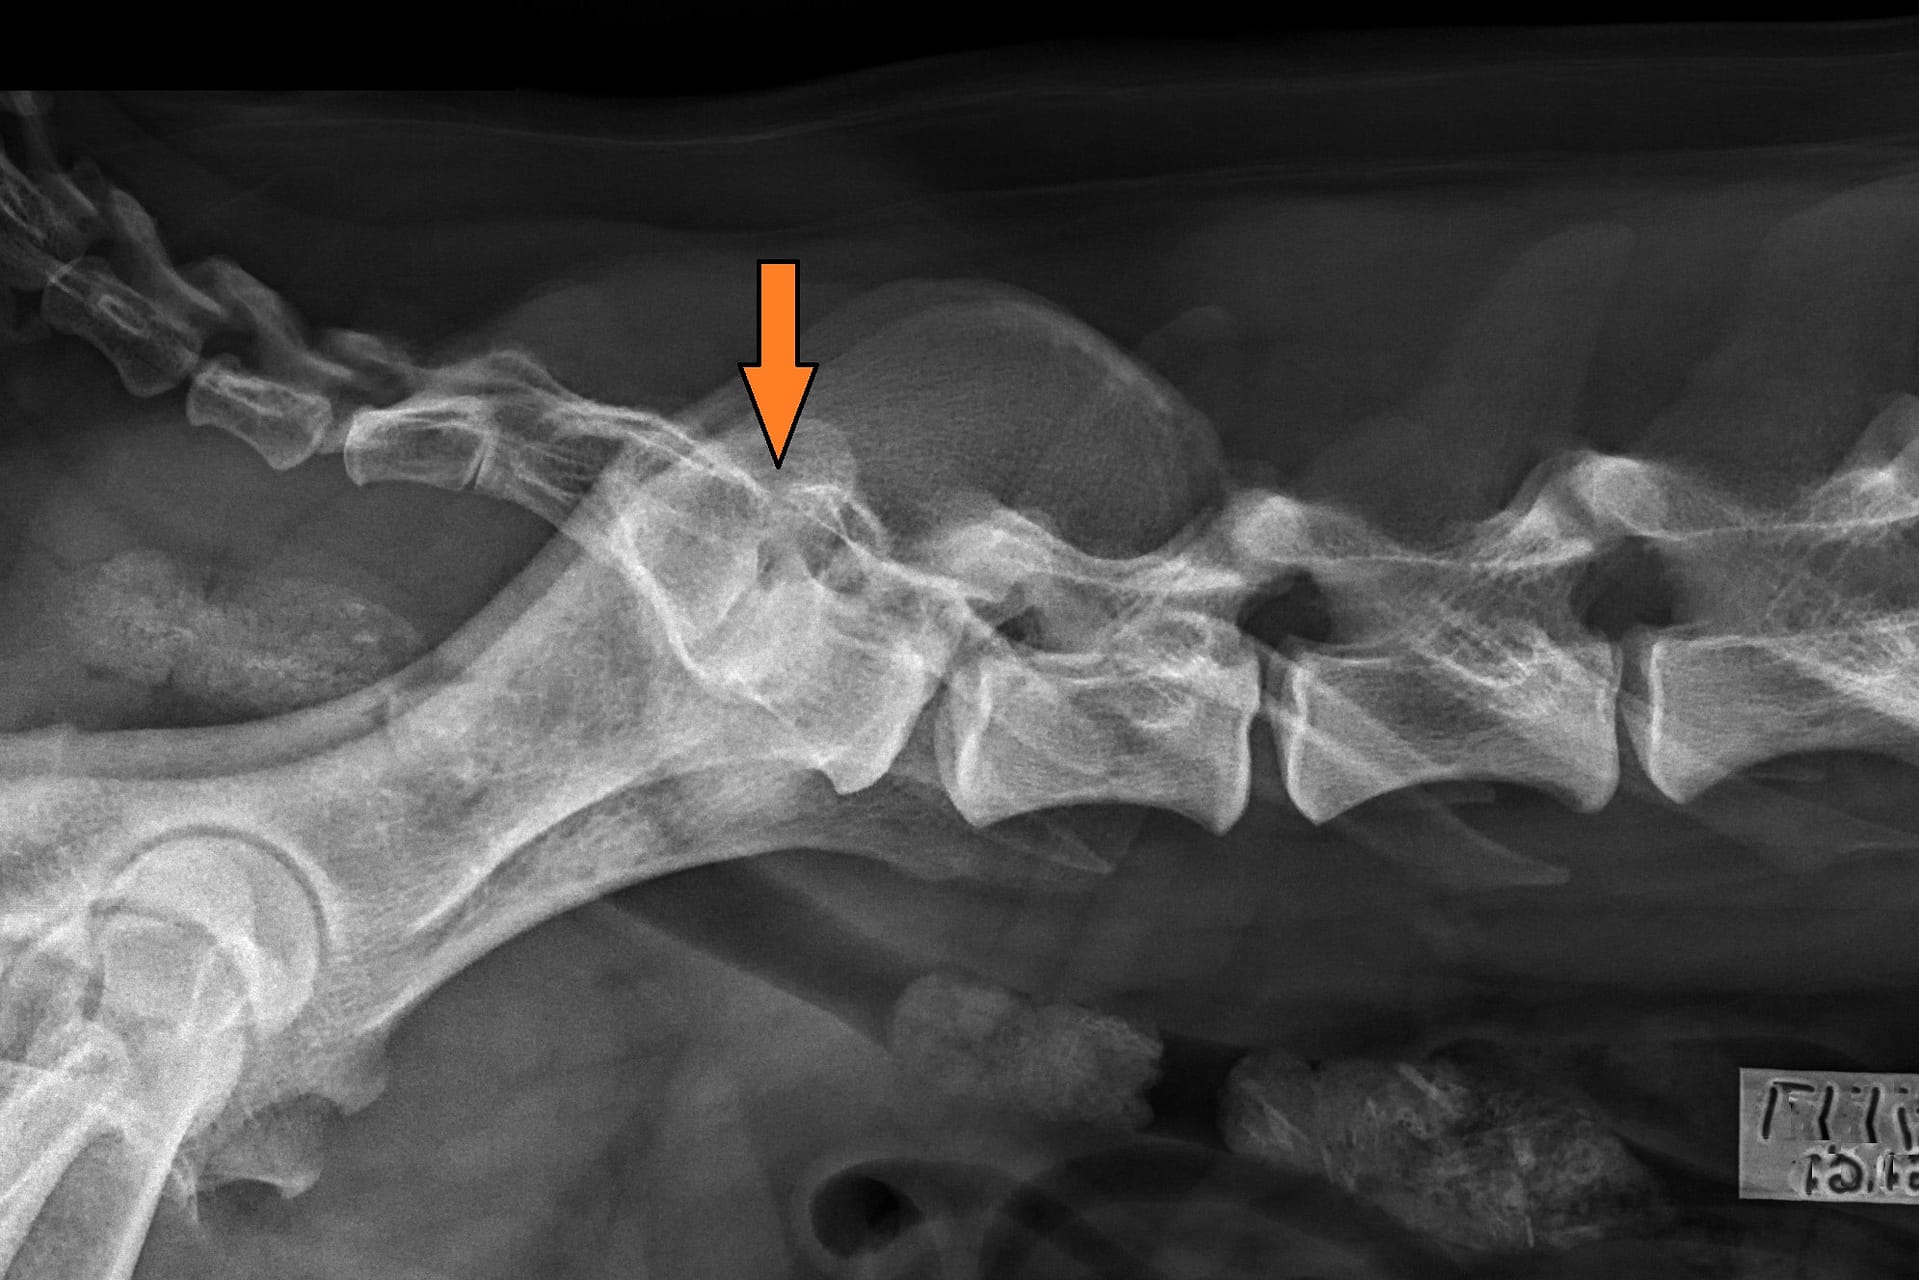

LTV3; asymmetrical; on the right in the VD photo the left side of S1 is shaped like a sacral vertebra and on the right side S1 is shaped like a lumbar vertebra including the spinous process.